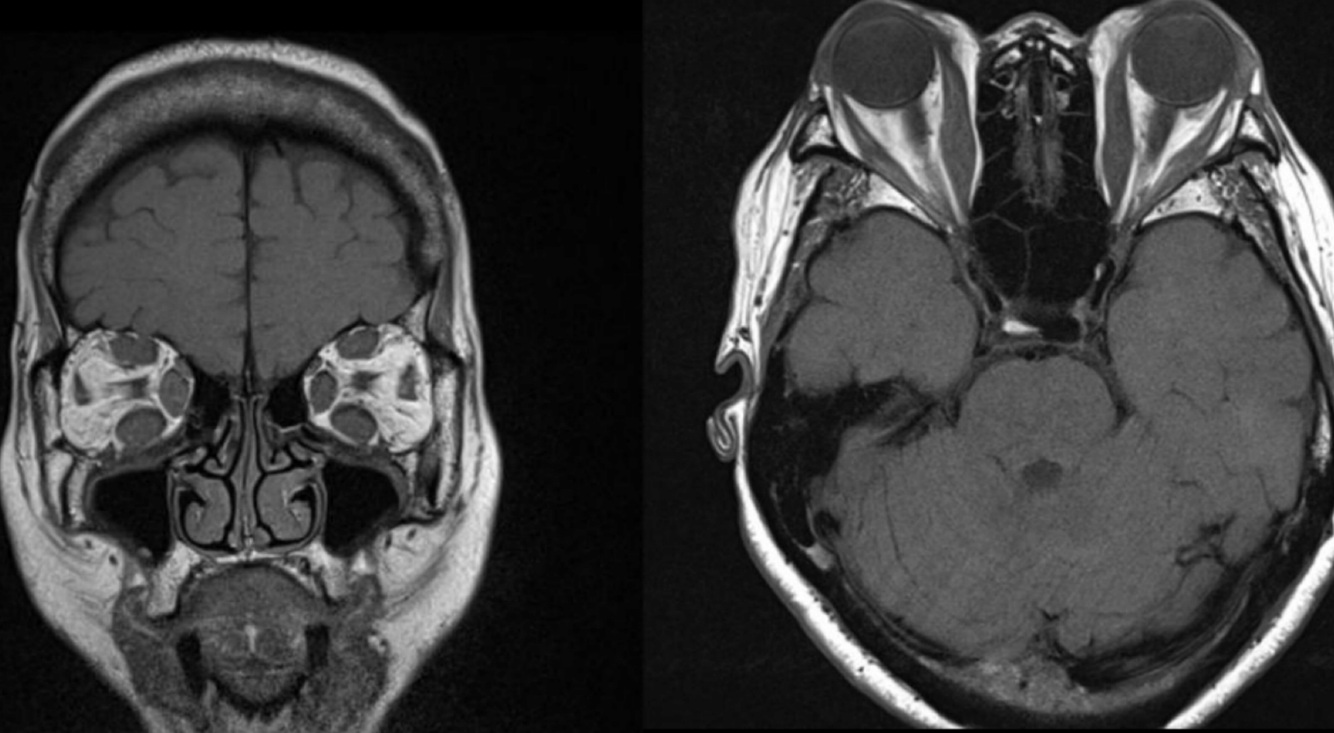

20

Q

Desprendimiento de retina

Hallazgos en TC/MRI

A

• Hiper densidad/intensidad

• Fluido subretiniano

• Neoplasias

• Retina triangular